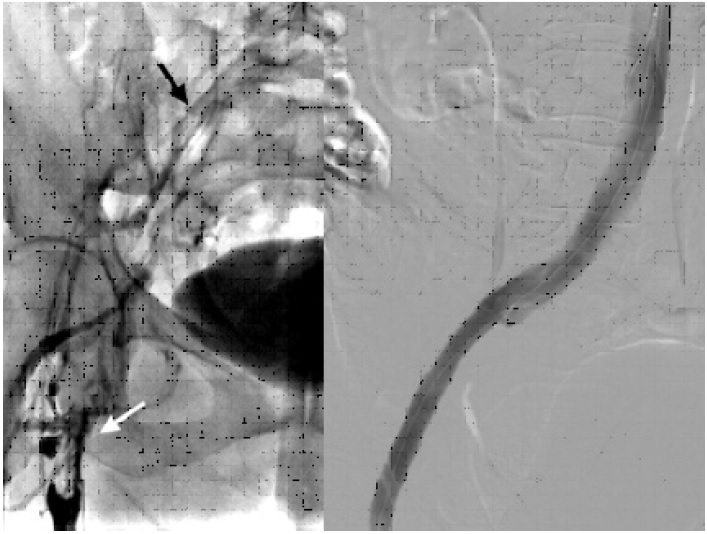

After treatment with LMWH for a week, there was a complete resolution of the thrombus (shown in Fig. 2). The patient was also seen in the immunohemotherapy clinic, and thrombophilia was discarded. After a 12-month follow-up, the patient remains asymptomatic and generally well.

Fig. 2 Left. Initial phlebography showing thrombosis from the proximal femoral vein (white arrow), which rechannels with low flow at the common iliac vein level (black arrow). Right. Final phlebography after stent placement showing absolute permeability of the iliac axis